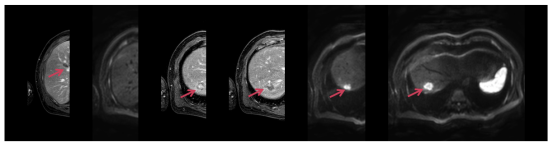

2023.12 PET-CT提示右肺新发数枚小结节,考虑转移。

image.png

图10 影像评估提示右肺新发数枚小结节,考虑转移

图11 影像评估提示右肺转移瘤粒子植入后病情稳定

2025.04 PET-CT提示右肺转移瘤较前增大。

图13 影像评估提示右肺转移瘤较前增大